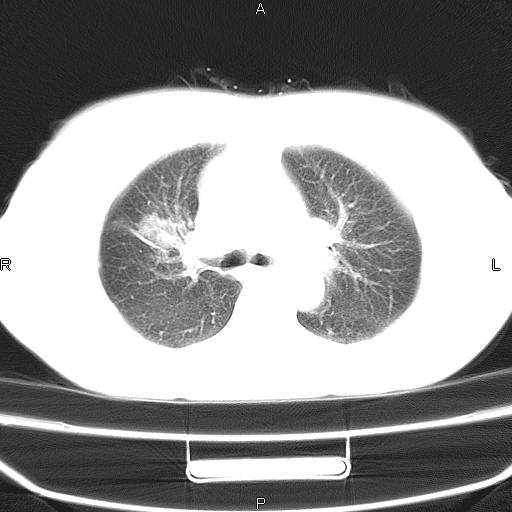

患者,女,66岁。健康体检胸部透视发现右上肺片状阴影。既往无不适,患者自诉三个月前曾有低热病史体温37.5左右一周。用药后缓解。至今无其它不适。请老师们指导指导。

考虑:右肺上叶周围型肺癌(分叶状肿块+砂粒状钙化+胸膜尾征)。

病灶见明显分叶、大小较大(大于3cm?),老年人,多考虑:肺癌,建议穿刺活检。

典型的中心型肺癌,尖段支气管阻塞。

右肺上叶周围型肺癌可能性大。

考虑:右肺上叶周围型肺癌